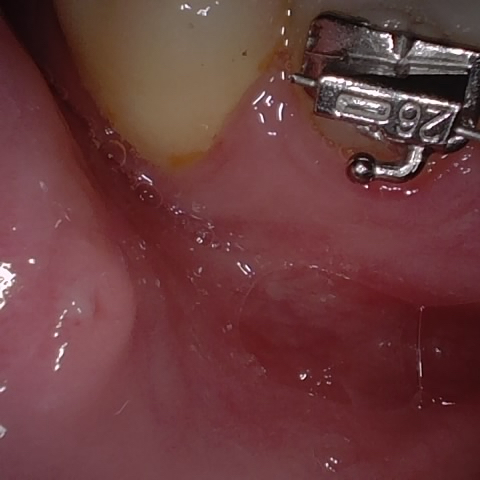

Annotated as "Bad"